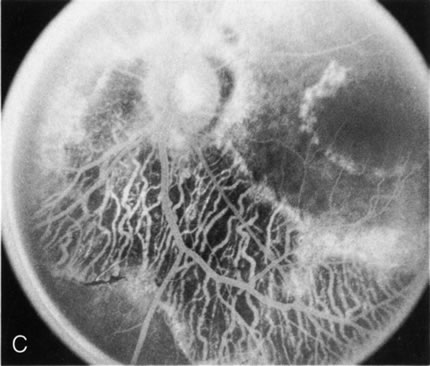

Fig. 1. Retinitis pigmentosa. A. A typical area of bone spicule pigmentation. B. Diffuse dye leakage is apparent throughout the posterior pole. C. The early angiogram shows dilated and irregular retinal radial peripapillary capillaries and perifoveal retinal capillaries. D. Leakage from these vessels are evident in the late angiogram.

Of more clinical importance is the role of FA in the diagnosis and treatment of cystoid macular edema (CME) (Fig. 1C and D). Stereoscopic FA indicates that the leakage, which may be diffuse or have the typical petaloid stellate appearance of CME, can come from the perifoveal retinal capillaries, from the choroid through the RPE, or from a combination of both sources.4 With the recent suggestion that CME in RP may be successfully treated with acetazolamide,5, 6 FA is thus important to document the diagnosis of CME, establish the origin(s) of leakage, and follow patients during and after therapy.